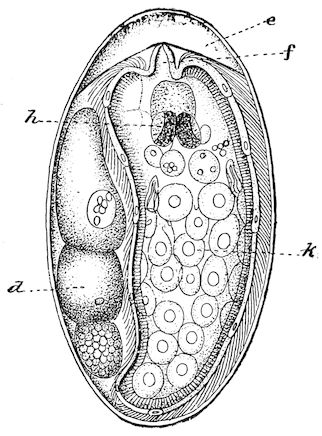

Fig. 3.—Pig suffering from osseous cachexia (fourth stage).

Such shocks would be of no importance to a healthy animal, but to one suffering from osseous cachexia, any violence, or even the slightest muscular effort may be followed by fracture of the gravest character, involving even the vertebral column. In cows the pelvis, femur, and tibia are most frequently injured.

In horses, particularly in riding horses, fractures are commonest in the region of the forearm, cannon bone, and anterior phalanges. So extremely fragile are the bones at this stage that the horse represented herewith broke twelve ribs at one time by simply falling on its side. It is interesting to note that such fractures are never accompanied by any extensive bleeding. They have little tendency to repair, no real callus formation occurs, and on post-mortem examination one often finds the ends unconnected by temporary callus, worn, and rounded by reciprocal friction.

At this stage but under other circumstances, the animals show great reluctance to rise, remaining down for twelve to twenty-four hours without shifting their position. If forced to get up, they stand as though fixed in one position, the respiration and circulation become rapid, and they soon grow tired and fall.

114. The fourth phase, or period of osteomalacia, i.e. softening of the bones, is also the last. It is rarely seen in large animals like horses and oxen, because accidents so often accompany the preceding stages and necessitate slaughter; but it is common in goats and pigs.

In this phase the bones become elastic, soft and depressible, yielding to the pressure of the operator’s fingers.

Fig. 4.—Deformity of the face in the horse shown in Fig. 2.

The flat bones are particularly liable to this change, which is common to domesticated animals. The bones of the head are the first to suffer; later those of the pelvis. The lower jaw becomes swollen, particularly about the centre of the branches which may attain three, four, or five times, their normal thickness.

The depression in the submaxillary space disappears. The upper jaw undergoes similar changes, becoming deformed and thickened until the cavities of the sinuses and the hollow appearance of the palate are lost, while the face is so changed that it cannot be recognised as that of a horse, goat, etc.

The molar teeth are almost buried, their tables alone being visible at the bottom of a depression, the edges of which rise above the neighbouring parts (pig).

Mastication is clearly impossible, the jaws appear paralysed, the muscles powerless, and only swallowing is possible, a fact which explains why life is only prolonged to this stage in animals which can be fed with a spoon or bottle (pigs and goats). The bones of the cranium, although greatly changed in texture, are always less deformed than those of the face.

The changes are such that it is often easy with a mere post-mortem knife to cut the head completely in two. Osseous tissue, properly so-called, has disappeared.

All the constituent tissues, with the exception of the skin and muscles, i.e., the bone, periosteum and aponeuroses, have the appearance and consistence on section of the fibro-lardaceous tissue seen in chronic inflammation.